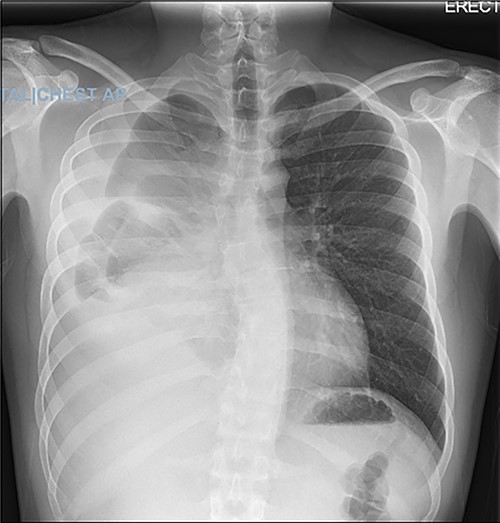

The patient was then turned to the supine position to resect the mediastinal mass, which started with a median sternotomy. The right pleural cavity was entered through the mediastinum, and the mass was mobilized from its adhesions to the chest wall. The lysis of adhesions was continued medially until the hilar structures were visualized. However, mobilization could not be achieved successfully without removing part of the lung that was extremely adherent to the mass. After removing this portion of the lung, the mass also demonstrated adherence to the right lateral aspect of the pericardium. Although multiple attempts were made to preserve the right phrenic nerve, a portion of it, along with part of the pericardium and small portion of normal-appearing thymus, had to be sacrificed due to surrounding inflammation and fibrosis. The mass was then able to be resected and removed, which was then sent for permanent pathologic examination (Fig. 4). before closure, staples were applied in the mediastinum and pericardial surface where the mass was attached to facilitate potential postoperative radiation.

Pathology from the permanent specimen demonstrated a partially encapsulated thymoma along with fibrotic bands that were composed of epithelioid epithelial cell proliferation mixed with many small lymphocytes. Ultimately, the mediastinal mass was determined to be a mixed type B2 and focal B3 thymoma.